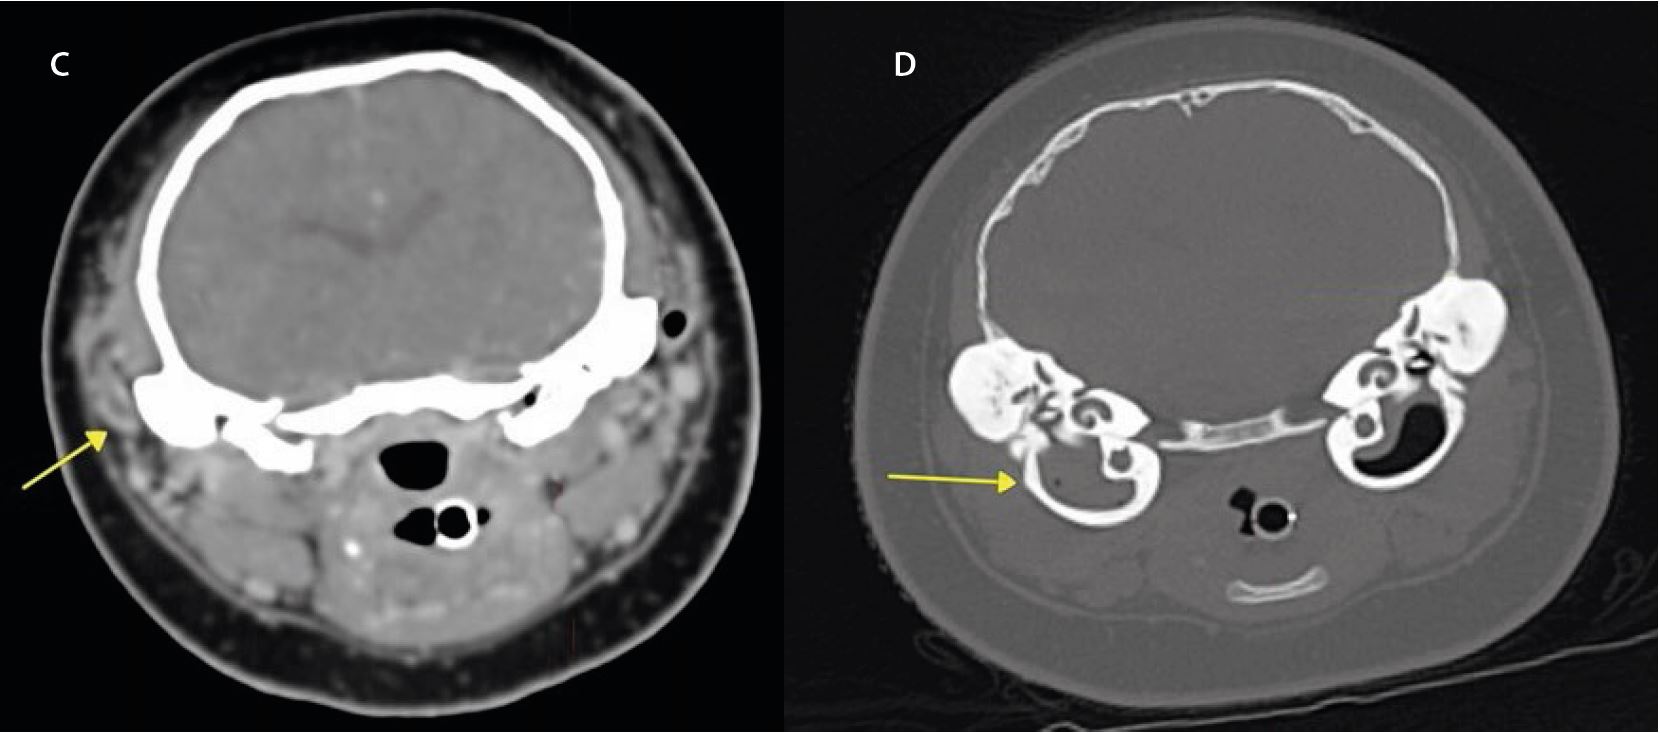

Каскаду було госпіталізовано з травмою голови, але без виділень з вух. КТ було використано для виключення середнього/ внутрішнього отиту. Поперечні та дорсальні КТ зображення показують нормальне ослаблення повітря в обох скроневих буллах (мал. 2). На основі КТ було виключено інфекцію середнього вуха. Також не було видимих   змін у тканині мозку.

Малюнок 2: Жодних аномалій не спостерігалося на обох реконструкціях кісткового фільтра